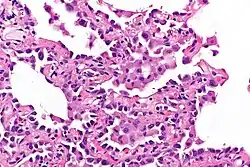

Micrograph showing multifocal micronodular pneumocyte hyperplasia. H&E stain.

• Well-demarcated, nodular lesions ranging 2–5 mm in pulmonary parenchyma.

• Type II pneumocytes without nuclear atypia lined thickened alveolar septa and proliferated papillary structures.

• Enlarged cuboidal cells lining mildly thickened alveolar septa.[11]

• Enlarged cuboidal cells have abundant, eosinophilic cytoplasm and large, round nuclei.[12]

• Papillary pattern with irregular margin and lymphocyte infiltration in the stroma.[13]

• No proliferation of immature smooth muscle cells suggestive of lymphangioleiomyomatosis.